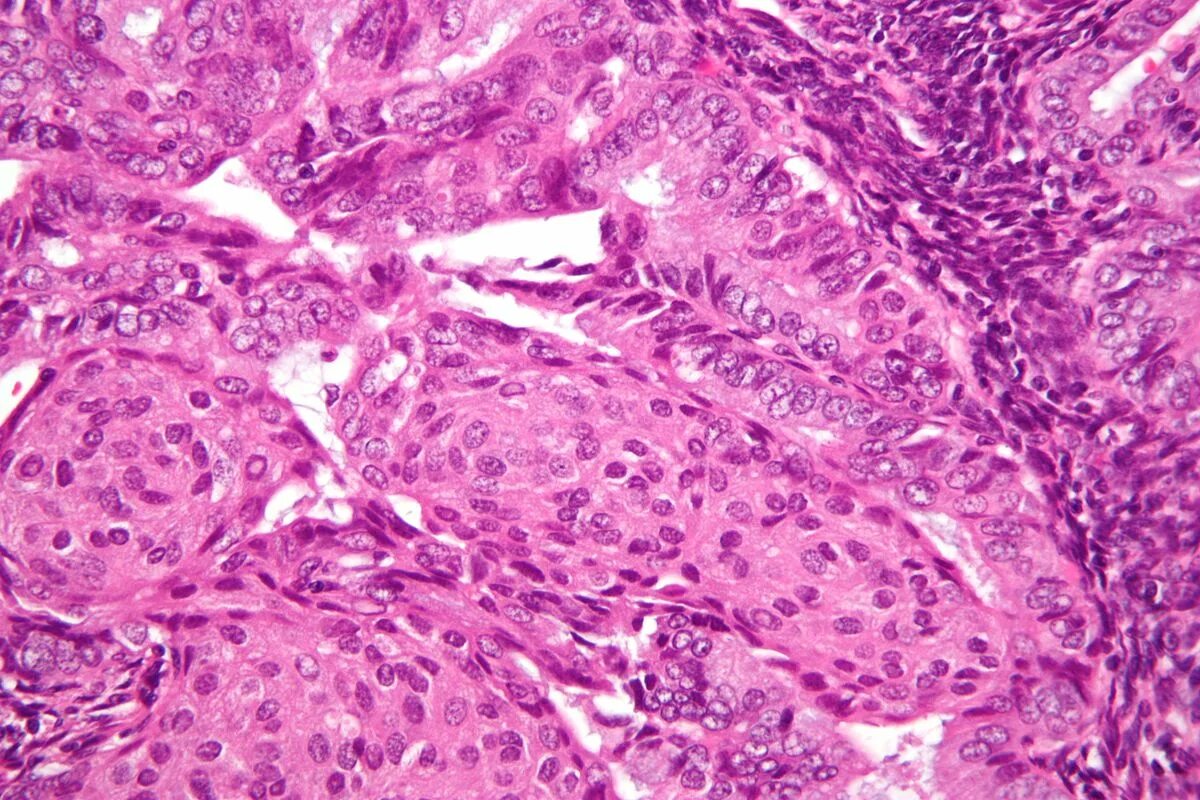

Гистология фото